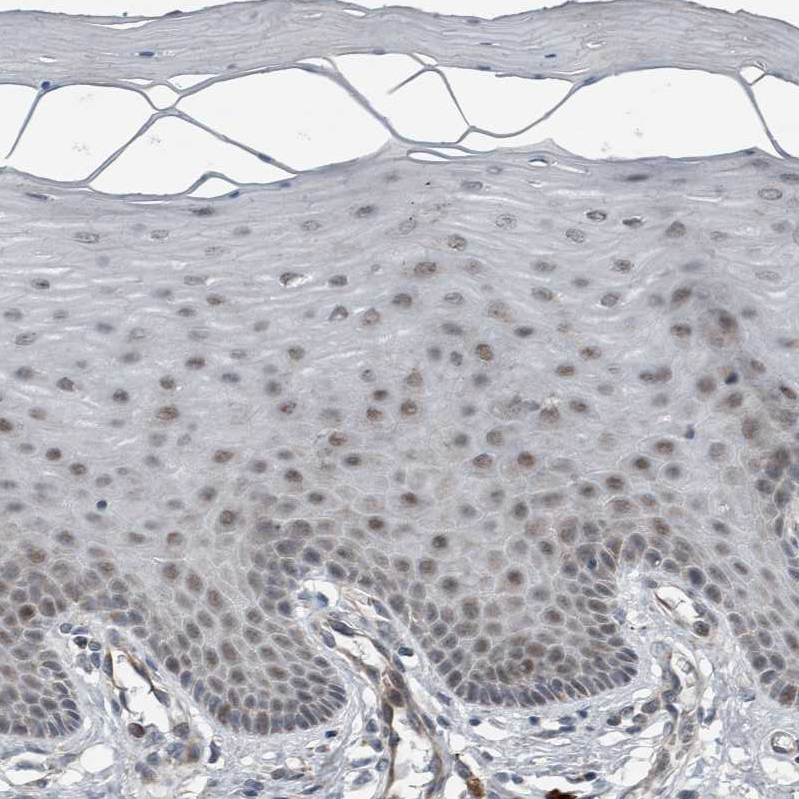

Immunohistochemical staining of human duodenum shows strong granular cytoplasmic positivity in goblet cells and enterocytes.